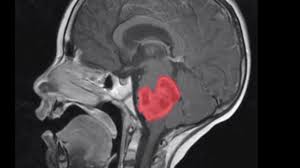

The signs may vary according to the type, size, and location of the tumor or the age of the child. Research indicates that prolonged, severe headaches that seem to worsen early in the morning or during physical activity could be a potential sign of brain cancer. They most commonly develop in children ages 5 to 8. The signs and symptoms of brain tumors vary widely, but include: This is the front of the brain.

Alan cohen, m.d., director of pediatric neurosurgery at johns hopkins children's center, shares the most common signs and symptoms that could point to a potential brain tumor. Some of the more common symptoms of a brain tumor in children include: Brain cancer is the most common form of cancer death in people under 40 and for such a serious disease, it hasn't received as much attention as other cancers. Symptoms from pediatric brain tumors vary widely, depending upon the tumor's location and size. Join david arons, ceo of the national brain tumor society, and the entire brain tumor community for an update on the progress we have made in the fight to conquer and cure brain tumors, and the critical work that lies ahead in 2021. A brain tumor can cause symptoms by directly pressing on the surrounding parts of the brain that control certain body functions, or by causing a buildup of spinal fluid and pressure throughout the brain (a condition known as hydrocephalus). A brain tumor is an abnormal growth of tissue in the brain. Sometimes, children with a brain stem glioma do not have any of these changes. Brain tumors are the second most common form of childhood cancer. Signs and symptoms may be caused by childhood brain stem gliomas or by other conditions. The cns also includes the spinal cord. Signs or symptoms vary depending on a child's age and the location of the tumor, but may include: The most common symptoms include:

Do You Recognize The 13 Early Signs Of Brain Tumor In Children Evaidya Health Articles from www.evaidya.com Brain tumors are the second most common form of childhood cancer. Research indicates that prolonged, severe headaches that seem to worsen early in the morning or during physical activity could be a potential sign of brain cancer. Headache many children with a brain tumor experience headaches before their diagnosis. It is a pivotal moment for our world, our nation, and our brain tumor community. Stage 1 is the least malignant stage of development: Signs and symptoms may be caused by childhood brain stem gliomas or by other conditions. Stage 2 is marked by the slow growth of cancer cells, which may spread into neighboring cells and develop into a higher stage of tumor that is more aggressive; Or, the cause of a symptom may be a different medical condition that is not a brain stem glioma.

Brain cancer is divided into four progressive and overlapping stages.

Sometimes, children with a brain stem glioma do not have any of these changes. Headaches that get worse over time are a common symptom of brain tumors. Take up space inside the skull when they grow cause specific symptoms due to the position of the tumour in the brain In general, brain tumors in children are very rare. Headaches, which may become more frequent and more severe feeling of increased pressure in the head unexplained nausea or vomiting Still, cancer is the second leading cause of death in children younger than 15 years old, after accidents. Symptoms may occur when a tumor presses on a nerve or damages certain parts of the brain. The cns also includes the spinal cord. Brain tumor signs and symptoms morning headache or headache that goes away after vomiting. Research indicates that prolonged, severe headaches that seem to worsen early in the morning or during physical activity could be a potential sign of brain cancer. Brain tumors are the second most common form of childhood cancer. Or, the cause of a symptom may be a different medical condition that is not a brain stem glioma. Infants and young children whose fontanels haven't yet closed may have virtually no detectable signs or symptoms of a brain tumor except for an increasing head circumference, which occurs because the skull expands as the tumor grows.

The symptoms of a pediatric brain tumor vary according to the size, type and location of the tumor. The main parts of the brain are: Check with your child's doctor if your child has any of the following: The cns also includes the spinal cord. The most common forms of brain tumors are: They may also occur when the brain swells or there is fluid buildup in the skull. Keep in mind, headaches are not usually early warning signs, but can occur once a tumor has reached a considerable size. Infants and young children whose fontanels haven't yet closed may have virtually no detectable signs or symptoms of a brain tumor except for an increasing head circumference, which occurs because the skull expands as the tumor grows. In children, tumors usually start in a part of the brain that controls movement and coordination. The brain is part of the central nervous system (cns). Brain cancer is an overgrowth of cells in your brain that forms masses called tumors. Take up space inside the skull when they grow cause specific symptoms due to the position of the tumour in the brain But not all brain tumors cause headaches, and most headaches are not caused by tumors.